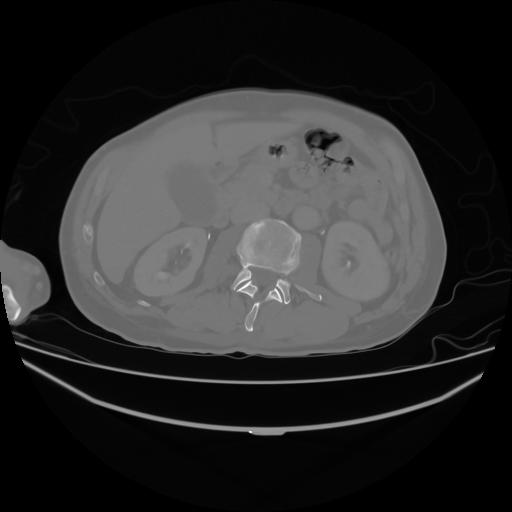

4 CUERPO,CE,Axial,3.0,CUERPO,,